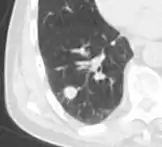

Lobulated nodule.[9]